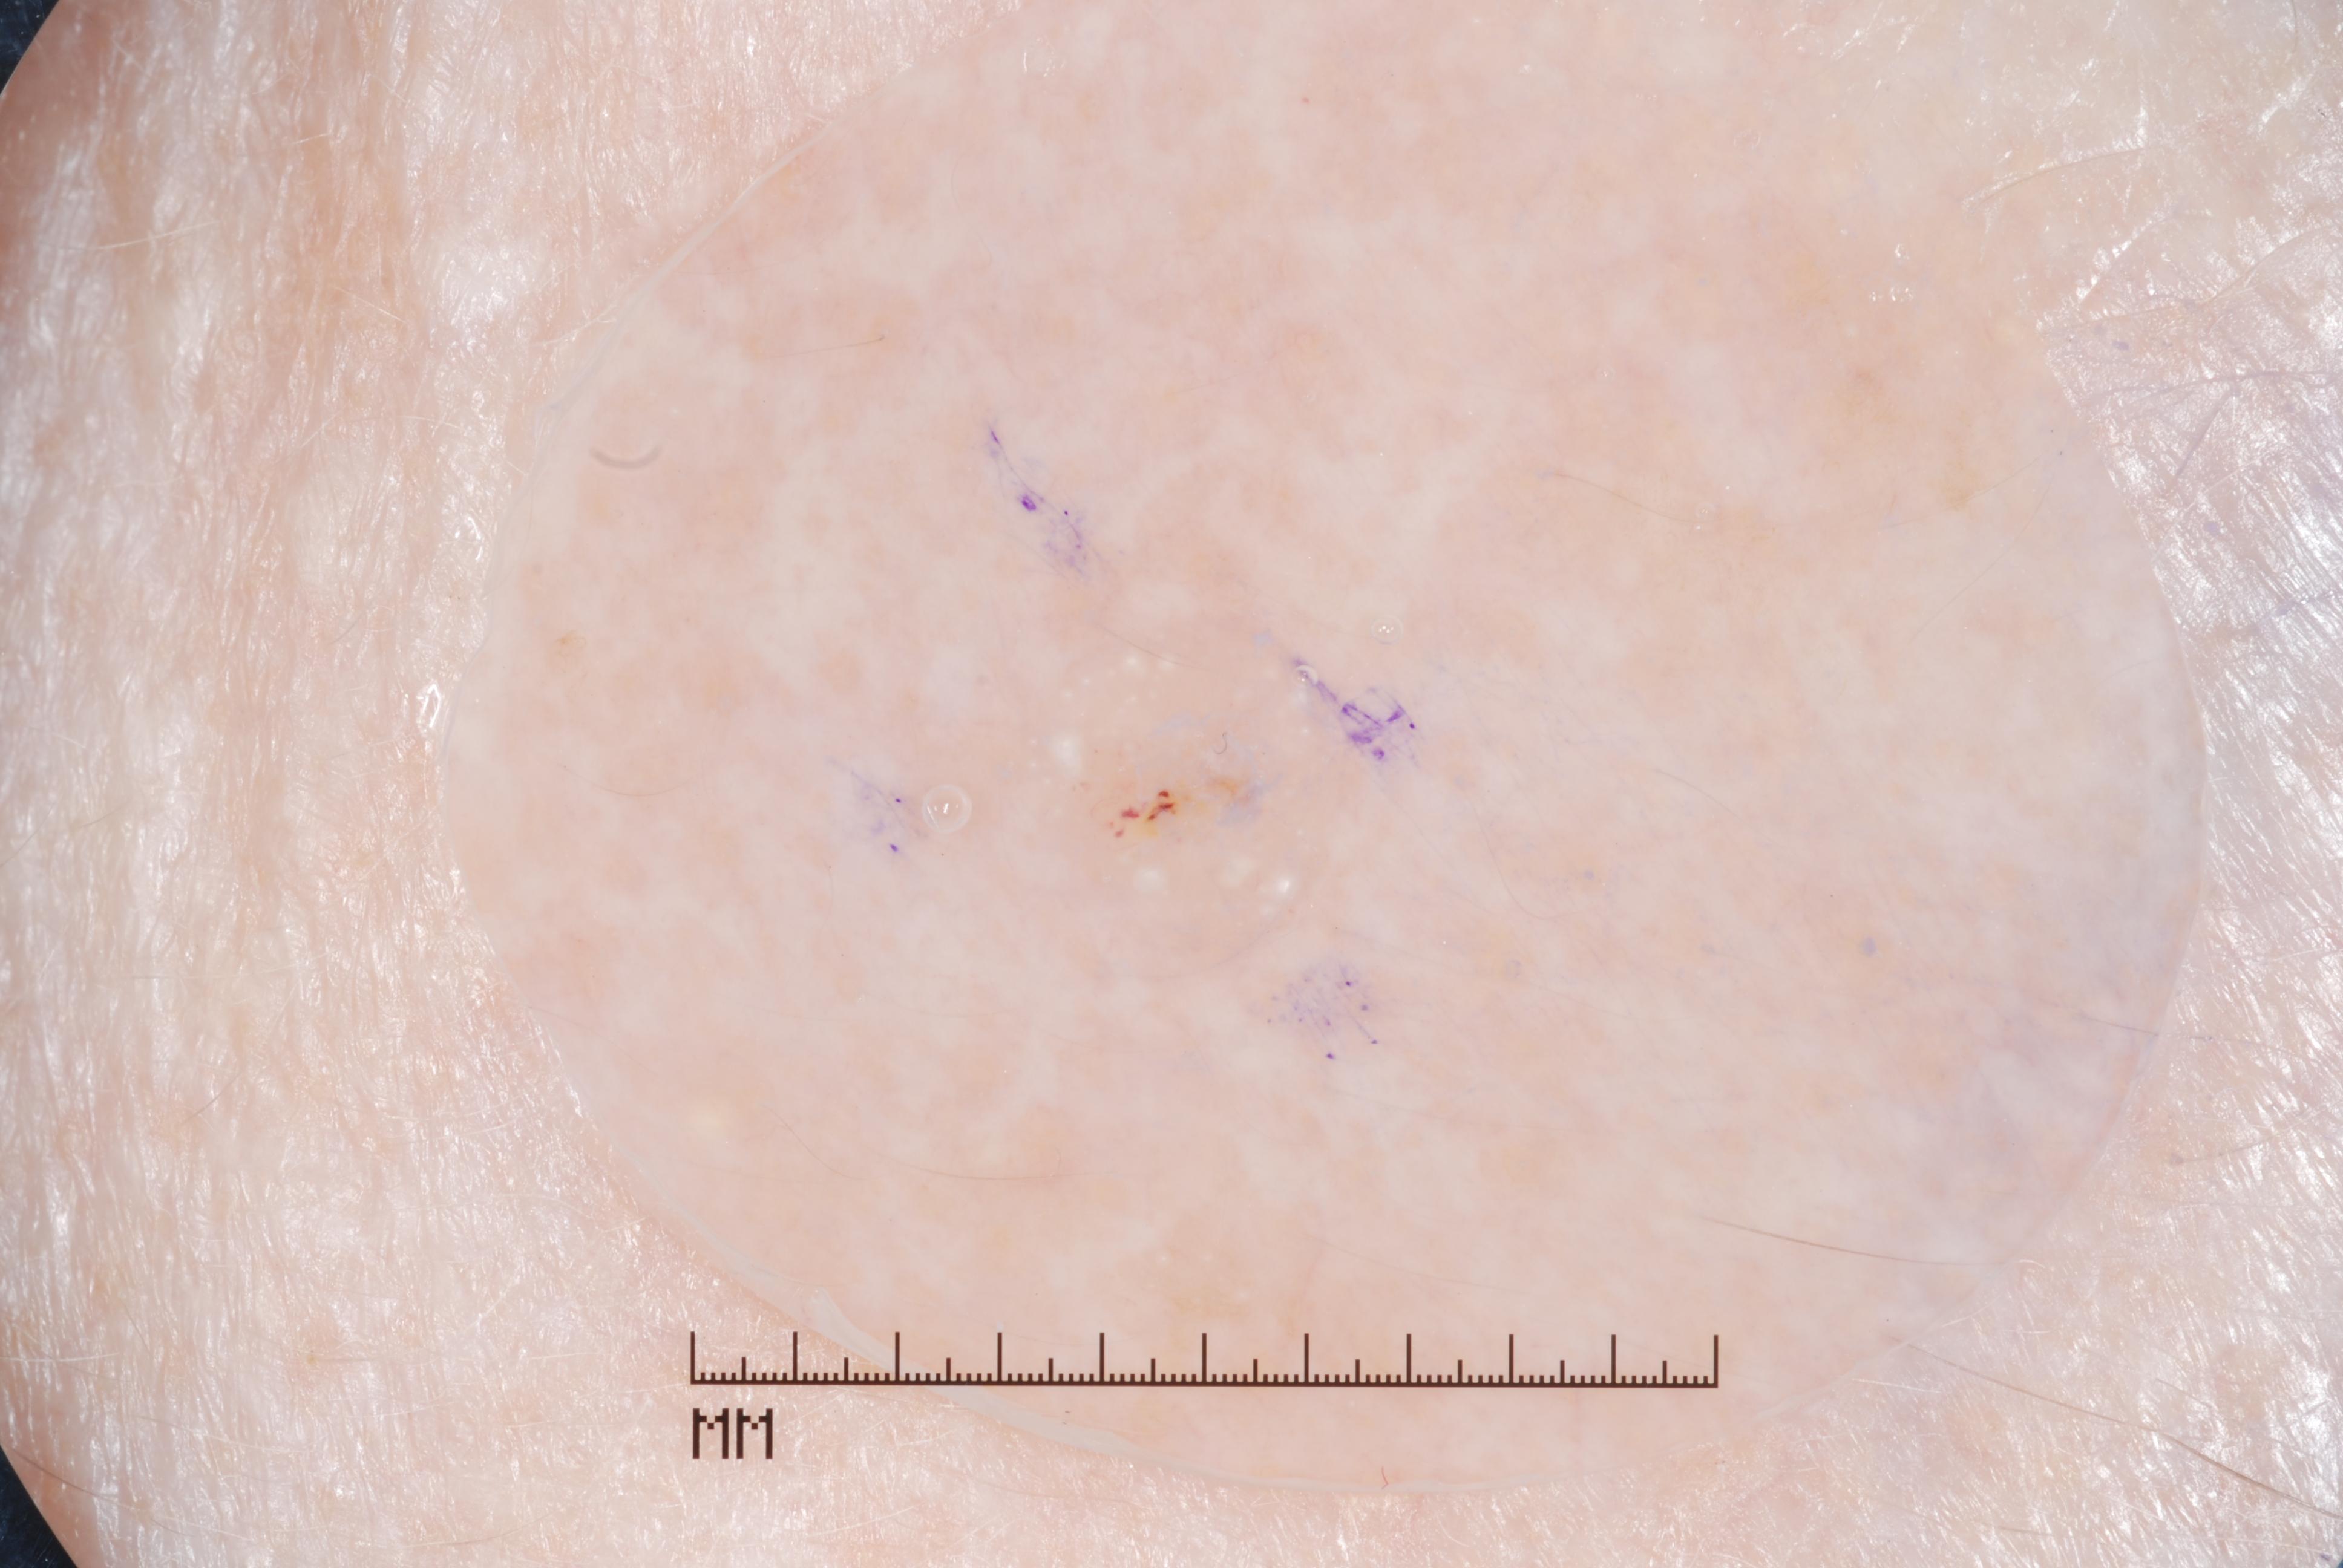

{

"age_approx": 55,

"anatom_site_general": "head/neck",

"concomitant_biopsy": true,

"dermoscopic_type": "contact non-polarized",

"diagnosis_1": "Benign",

"diagnosis_2": "Inflammatory or infectious diseases",

"diagnosis_3": "Verruca",

"diagnosis_confirm_type": "histopathology",

"image_type": "dermoscopic",

"lesion_id": "IL_0853918",

"melanocytic": false,

"sex": "male"

}